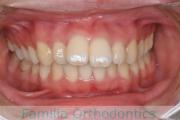

上の前歯が出ているのと下の前歯のでこぼこを治したいということで来院されました。左右のズレがあるので、上顎を左右から、下顎は左下のみ小臼歯を抜歯して、アンカースクリューを併用したマルチブラケット法にて治療を行いました。2年強、25回程度の通院が必要でした。

前歯の移動量が多いケースとなりますので、歯根吸収や歯肉退縮のリスクが高めです。